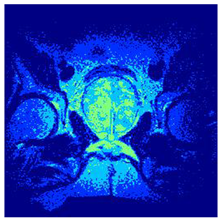

| Image | nt = 3 | nt = 4 | nt = 5 | nt = 8 |

|---|---|---|---|---|

| 1 | ![]() | ![]() | ![]() | ![]() |

| 2 | ![]() | ![]() | ![]() | ![]() |

| 3 | ![]() | ![]() | ![]() | ![]() |

| 4 | ![]() | ![]() | ![]() | ![]() |

| 5 | ![]() | ![]() | ![]() | ![]() |

| 6 | ![]() | ![]() | ![]() | ![]() |

| 7 | ![]() | ![]() | ![]() | ![]() |

| 8 | ![]() | ![]() | ![]() | ![]() |

| 9 | ![]() | ![]() | ![]() | ![]() |

| 10 | ![]() | ![]() | ![]() | ![]() |

| 11 | ![]() | ![]() | ![]() | ![]() |